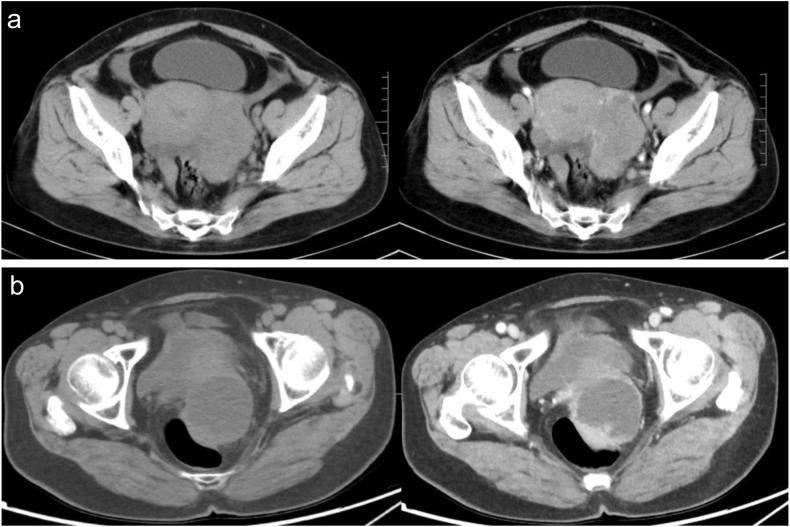

Prognostic models play a crucial role in providing personalised risk assessment, guiding treatment decisions, and facilitating the counselling of patients with cancer. However, previous imaging-based artificial intelligence models of epithelial ovarian cancer lacked interpretability. In this study, we aimed to develop an interpretable machine-learning model to predict progression-free survival in patients with epithelial ovarian cancer using clinical variables and radiomics features. A total of 102 patients with epithelial ovarian cancer who underwent contrast-enhanced computed tomography scans were enrolled in this retrospective study. Pre-surgery clinical data, including age, performance status, body mass index, tumour stage, venous blood cancer antigen-125 (CA125) level, white blood cell count, neutrophil count, red blood cell count, haemoglobin level, and platelet count, were obtained from medical records. The volume of interest for each tumour was manually delineated slice-by-slice along the boundary. A total of 2074 radiomic features were extracted from the pre- and post-contrast computed tomography images. Optimal radiomic features were selected using the Least Absolute Shrinkage and Selection Operator logistic regression. Multivariate Cox analysis was performed to identify independent predictors of three-year progression-free survival. The random forest algorithm developed radiomic and combined models using four-fold cross-validation. Finally, the Shapley additive explanation algorithm was applied to interpret the predictions of the combined model. Multivariate Cox analysis identified CA-125 levels (P = 0.015), tumour stage (P = 0.019), and Radscore (P < 0.001) as independent predictors of progression-free survival. The combined model based on these factors achieved an area under the curve of 0.812 (95 % confidence interval: 0.802-0.822) in the training cohort and 0.772 (95 % confidence interval: 0.727-0.817) in the validation cohort. The most impactful features on the model output were Radscore, followed by tumour stage and CA-125. In conclusion, the Shapley additive explanation-based interpretation of the prognostic model enables clinicians to understand the reasoning behind predictions better.